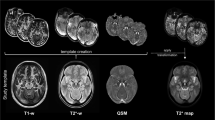

A study specific T1-weighted template was created from individual MPRAGE images from 31 patients and 22 healthy control participants using rigid, affine, and nonlinear diffeomorphic registration (greedy symmetric normalization, SyN) with five resolution levels. All participants MPRAGE reference images were normalized to this study specific template using an identical approach as the one used for creating the template. The study specific T1-weighted template was registered to the MNI 0.5 mm ICBM152 (International Consortium for Brain Mapping) T1-weighted, non-linear, asymmetric template again using rigid, affine and non-linear registration to bridge the normalization of individual T1-weighted images88. Finally, we concatenated transformations from within-subject registration and to-template normalization to normalize all images to MNI template space for analysis, and created MT-weighted, R2* map and quantitative susceptibility map templates by averaging normalized images from all healthy participants (Fig. 1b, top row).

a A midbrain search-space (green) and lateralized cylindrical reference regions (blue and red) were manually defined on the MNI-template and used to calculate lateralized MT CNR maps of the midbrain. b For the ROI analysis in patients, the ROIs were defined manually on MT-weighted, high-resolution QSM and low-resolution R2* templates constructed by averaging data from all healthy controls. For each modality an ROI was defined for the right (blue) and left (red) SN and N1 (based on dorsal nigral hyperintensity, low quantitative susceptibility and low R2* for the MTw, QSM and R2* modalities respectively). Mean MT CNR, R2* and QSM values were extracted from each lateralized ROI for the assessment of correlations with contralateral motor severity and motor asymmetry.